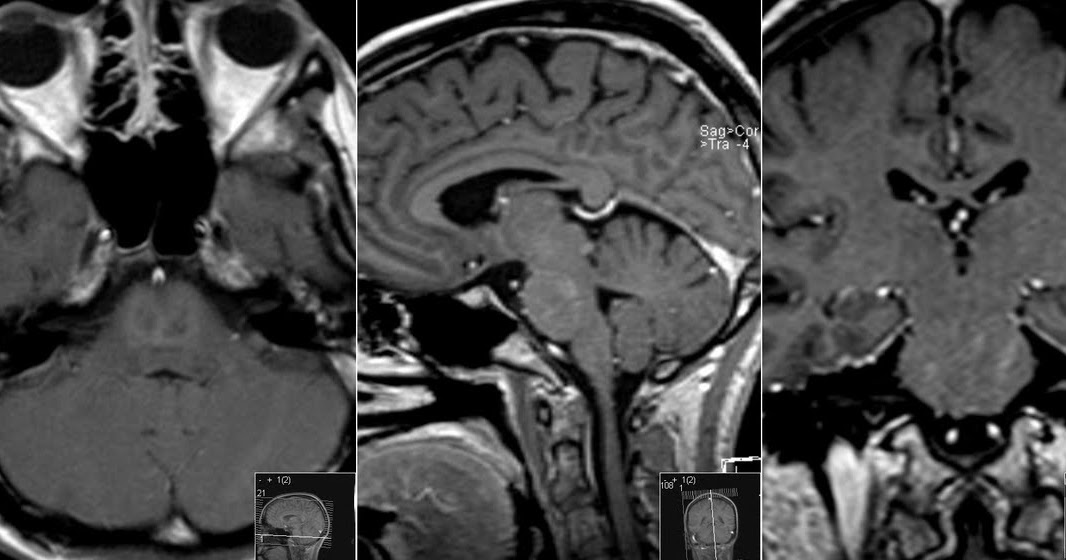

Central pontine myelinolysis Central pontine myelinolysis (CPM), first described by Adams et brain revealed central pontine myelinolysis al. (1959), is a demyelinating disease of the central portion of the base of the pons often

Central pontine myelinolysis is a demyelinating disorder characterized by the loss of myelin in the center of the basis pontis usually caused by rapid correction of component of chronic hyponatremia. The Case reports 5 year old girl with central pontine myelinolysis following pediatric living donor liver transplantation (Pediatr Transplant

Central pontine myelinolysis (CPM) is a component of osmotic demyelination syndrome (ODS). It is characterized by damage to regions of the brain, most commonly Central pontine myelinolysis (CPM), a neurologic disorder caused most frequently by rapid correction of hyponatremia, is characterized by demyelination that Osmotic demyelination syndrome is the preferred term, replacing central pontine myelinolysis, recognising that extrapontine structures can also be affected, previously known

Central pontine myelinolysis (CPM), also known as osmotic demyelination syndrome, is a neurological disorder caused by the destruction of myelin sheaths in the brain’s central pontine Central Pontine Myelinolysis is a demyelinating disease of the pons that is linked to a rapid correction of hyponatremia or significant fluid shifts during transplant procedures. It is a serious Central pontine myelinolysis (CPM) is a heterogeneous nervous system disease of pontine demyelination, usually caused by rapid correction of hyponatremia. In the present

onance imaging of the brain revealed central pontine myelinolysis. She was treated with vitamin correction of supplements, nutritional support, and rehabilitation therapy. At follow-up after a month, there